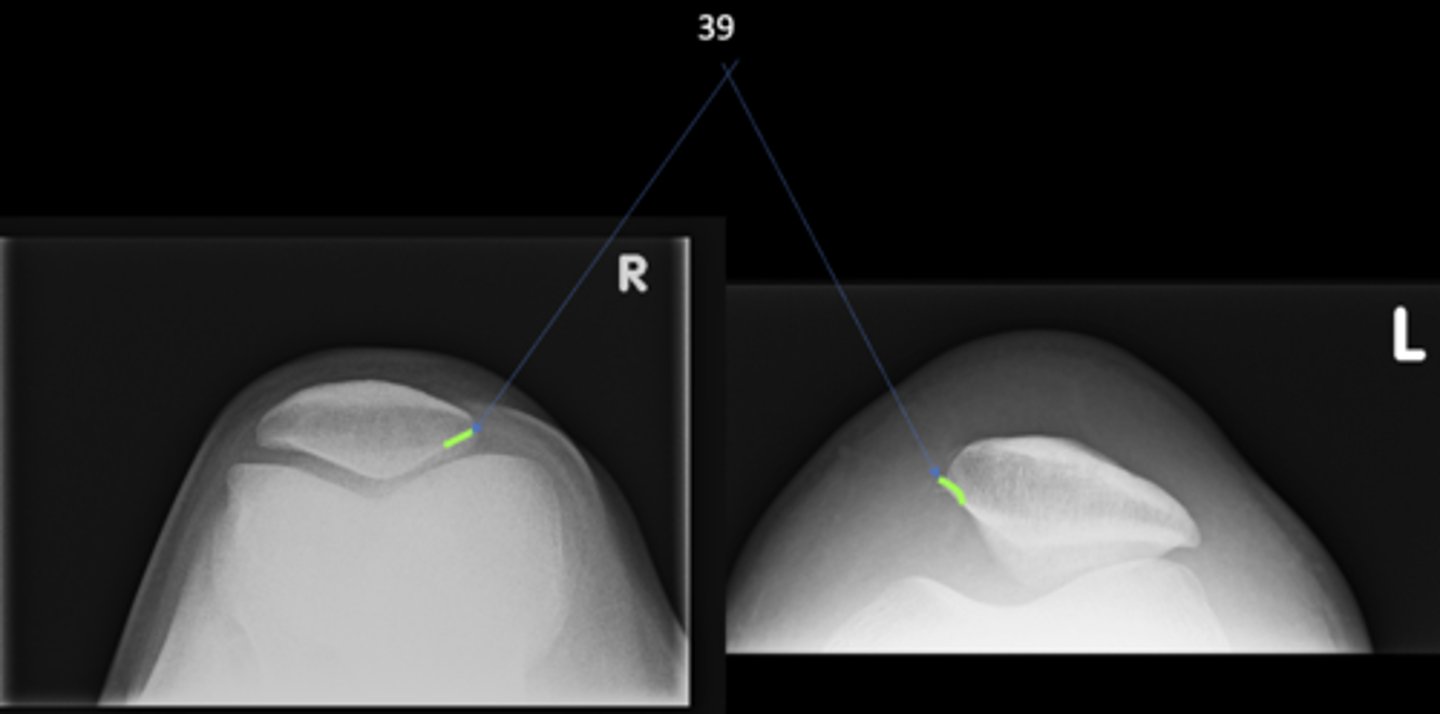

New cards

No

Are there any supplementary unilateral hip projections?

14

Sunrise (tangential) knee

ID supplementary knee projection

<p>ID supplementary knee projection</p>

Patellofemoral joints

Sunrise knee projections help see the _____

<p>Sunrise knee projections help see the _____</p>

Medial patellofemoral joint

ID 37 (joint)

<p>ID 37 (joint)</p>

Lateral patellofemoral joint

ID 38 (joint)

<p>ID 38 (joint)</p>

Odd facet

ID 39

<p>ID 39</p>